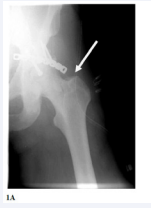

A 50-years old polytrauma patient with intra-articularfracture of the left acetabulum and fracture of the contralateral forearm, who initially was operated in another trauma center, was referred to our orthopedic department one week after his accident because of drop-foot of the operated limb. The surgery occurred six hours after a road traffic accident and included an open reduction and internal fixation of posterior - superior acetabular rim fracture with plate and screws (Figure 1A)

Figure 1: (A): Insufficient fixation of acetabular fracture with long and not properly contoured plate. Notice the lateral end of the plate being not attached to underlying bone (arrow).

as well as internal fixation of both bones of his forearm with plate and screws (not shown).

Our case examination revealed that according to his medical reports, the patient had not any neurovascular malfunction before these operations and his inability to dorsiflex his ankle joint as well as sensory deficit in the common peroneal nerve dermatomes, were diagnosed immediately after his recovery in the operating theatre. The electromyography findings, that were performed 10 days after the initiation of his symptoms, indicated dysfunction of the peroneal nerve at the level of the hip operation. The x-ray documented sufficient reduction of the fracture but insufficient (size and position of the plate) fixation (Figure 1A). Through the same Kocher Langebeck approach, which was previously used for primary fracture platting, the fixation metalwork was dissected. The sciatic nerve was found to be uncut but edematous lying underneath the lateral end of the plate which was not in contact to the underlying bone (long mal-positioned plate not properlycurved – Figure (1A) arrow). The plate was carefully removed and a new reconstruction plate, properly curved was used with screws for fracture fixation (Figure 1B).

Figure 1B: After revision of fixation with properly curved and positioned reconstruction plate and screws.